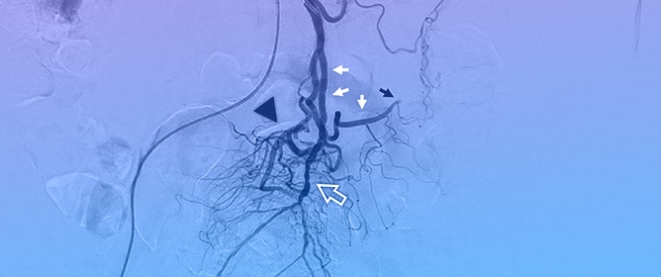

Background/Objectives: Endoscopic biliary stenting is the standard palliative intervention for malignant biliary obstruction, aimed at restoring ductal patency. Radiofrequency ablation (RFA) has been introduced as an adjunct technique to improve stent durability and patient outcomes. However, the literature remains inconclusive regarding which patients are most likely to benefit from the combination of RFA and stenting. Methods: We retrospectively described clinical outcomes of 24 patients undergoing endobiliary RFA combined with biliary stenting for malignant biliary obstruction. Post-procedural and 6-month outcomes were assessed using technical success and changes in serum bilirubin; procedure-related adverse events were extracted from available medical records. Results: Nineteen females and five males were included in the study. The most prevalent diagnoses were metastatic adenocarcinoma (n = 8) and cholangiocarcinoma (n = 6). 25% of patients did not complete the 6-month follow-up due to malignancy progression. 16 out of 18 maintained the patency of biliary stents. Repeat endoscopic intervention for suspected stent dysfunction was documented in one patient. When analyzed in an intention-to-treat manner (counting deaths before 6 months as failures), the corresponding 6-month patency/clinical success rate was 16/24 (66.7%). Conclusions: In this retrospective single-center experience, RFA combined with biliary stenting was feasible and was associated with maintained biliary drainage in a majority of patients who survived to the 6-month assessment.